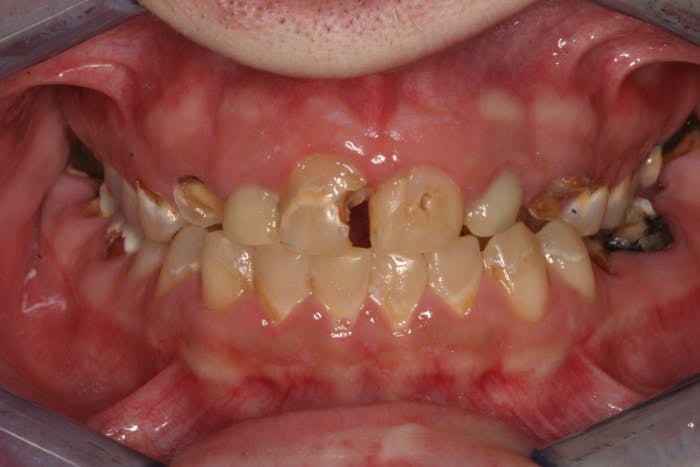

In another example, a young patient had been using e-cigarettes for five years. He started vaping as a method to quit smoking traditional tobacco products thinking vaping was a healthy alternative. Because of its ease of use, he smoked a cartridge of one of the more popular vaping products a day. Admittedly, he also drank energy drinks (high sugar content), stating that his mouth was often dry after vaping. This combination led to rampant decay with smooth-surface lesions and future tooth loss (figure 3).

Figure 3: Effects of e-cigarettes